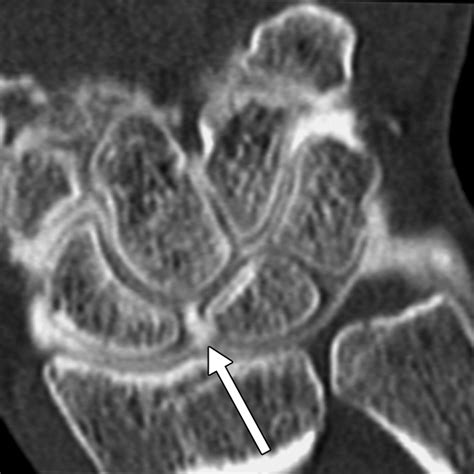

Diagnosing a Scapholunate Ligament Tear involves a combination of physical examination and imaging tests. The diagnostic process typically includes:

• Imaging Tests: X-rays, MRI, and CT scans can provide detailed images of the wrist, helping to confirm the diagnosis and assess the extent of the injury.